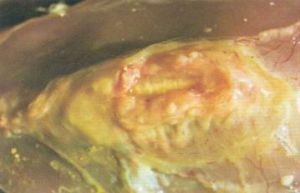

滑液霉形體(支原體)感染——病雞關節病變 潛伏期5~10天。典型發病是急性,然後轉為慢性。病雞食慾、飲欲良好,但精神不振,生長停滯,消瘦,脫水,雞冠蒼白,嚴重時呈紫紅色;常腹瀉,糞便含有大量白色尿酸鹽並帶青綠色。同時,跗關節腫脹,跛行,癱瘓。胸骨脊部有時出現起泡或硬結,繼而軟化為囊腫。在全身症狀有所好轉後,關節腫脹與跛行持續很久。病菌主要侵害跗關節和爪墊,嚴重時引起滲出性滑膜炎、滑液囊炎和腱鞘炎。

滑液霉形體(支原體)感染——病雞關節病變 脾、肝、腎腫大,氣囊有時混濁增厚。受侵害關節常見腱鞘炎、滑膜炎和骨關節炎。受害關節腔內、滑液囊、肌腱鞘(龍骨也有)有灰白色滲出物或乾酪樣物質,有時關節腔內乾燥無滑液,跗關節、足掌腫脹,足趾下有時潰破,結痂。胸部常見囊腫。重症在頭頂和頸上方出現乾酪樣物。受影響的關節色黃紅,有時關節軟骨糜爛。